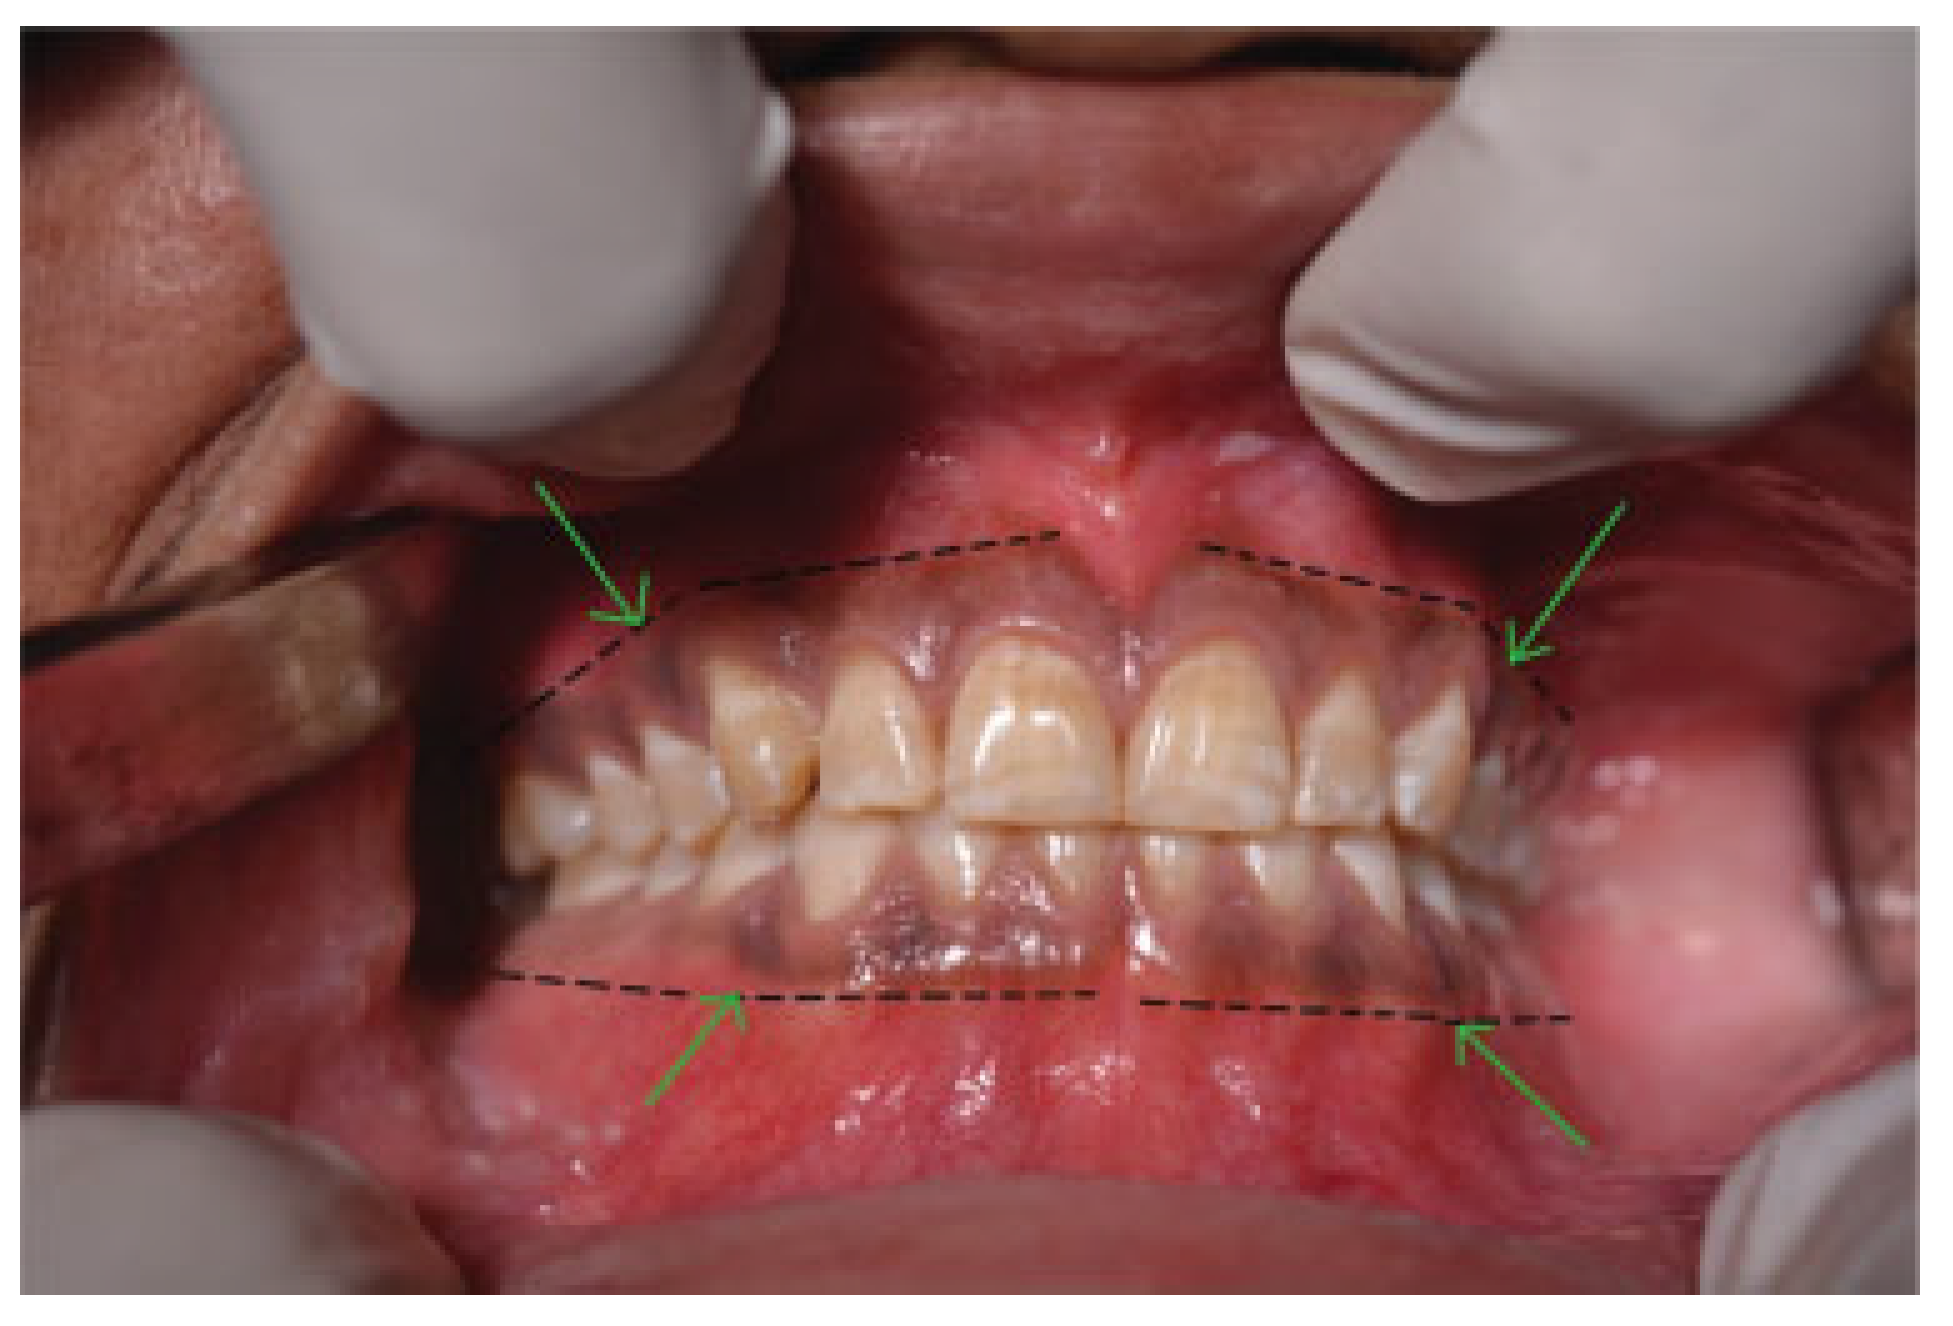

![]() |